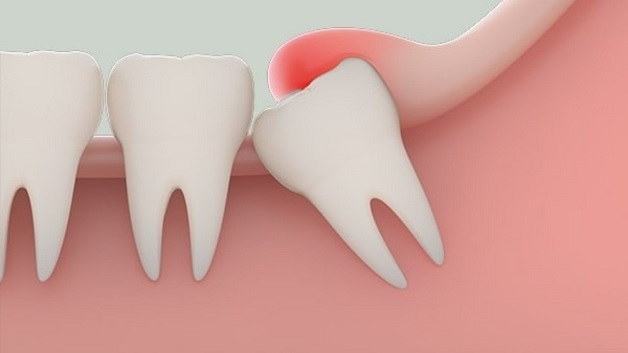

Do răng khôn thường mọc sau các răng vĩnh viễn khác, khi xương hàm đã phát triển hoàn thiện và ổn định. Do đó khi mọc, chúng sẽ thiếu không gian, phải chen đẩy vào những răng khác.

Chính vì vậy mà răng khôn thường không mọc thẳng mà sẽ mọc cong vẹo, mọc lệch, mọc ngầm gây đau đớn, khó chịu, hỏng cấu trúc hàm và có khi là bệnh lý cho người bệnh. Ngoài ra, có nhiều trường hợp răng khôn mọc còn gây nhiễm trùng lan sang vùng cổ, mắt, mang tai, má,… Nếu nhiễm trùng không điều trị kịp thời sẽ để lại những di chứng nguy hiểm, thậm chí tới tính mạng.

Răng khôn nằm ở vị trí phía cuối hàm